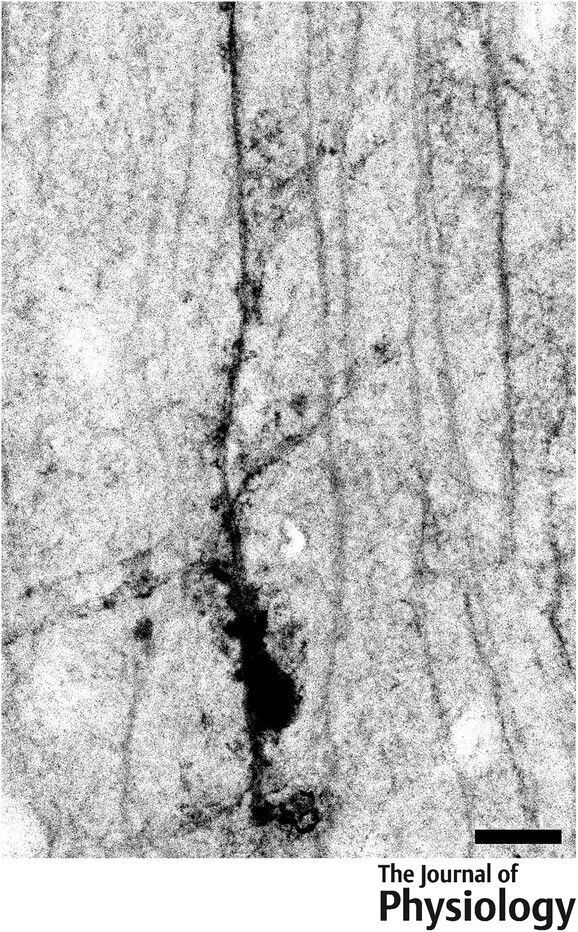

@JPhysiol

Journal of Physiology

10 months

A. Singer (of @univ_paris_cite) et al. present a first morphological and electrophysiological characterization of Fañanas cells of the mouse #cerebellum 🧠 🔬 Read the #Research here: https://t.co/0Ylt61fiIR